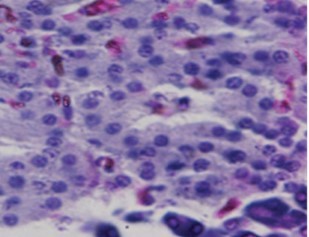

No comparable significant change observed in the mean weights of the extracted pancreas. The photomicrographs (Figure 4, Figure 5, Figure 6 and Figure 7) of the pancreatic tissue histology revealed preserved histoarchitecture in DSE and DEE groups as compared with the normal appearance of pancreas histoarchitecture from a normal healthy Wistar rat. Photomicrograph of the pancreas from diabetic control (DC) rats (Figure 7) shows distorted Islet margin with lymphocytic cells infiltration and moderate necrotic parenchyma.

Figure 7.Photomicrograph of the pancreas from diabetic control (DC) rats showing distorted Islet margin (arrow) with lymphocytic cells infiltration and moderate necrotic parenchyma (H &E stain X400 magnification)

Due to different species of garden egg in nature, likelihood of variation in its effect on weight reduction is expected. There is an uncited claim by some nutritionists that green garden egg species works better for weight loss compared to other species. However, findings obtained in our study using the white species with green stripes (S. aethiopicum L) revealed a remarkable reduction in weight gain in diabetic rats. Though, our present study did not compare species effect on weight gain, in our subsequent research however, we shall conduct a study to correlate species and weight-lowering effect. Meanwhile, based on the present outcome of this study, recommendation of the white-with-green-striped species should be encouraged for beneficial optimal effect on weight reduction. The beneficial impacts of S. aethiopicum on glycemic status and profile are depicted in Table 3 and Figure 2. The mean FBS concentrations decreased significantly (P < 0.05) in both DEE and DSE groups (DEE >> DSE, P = 0.025) compared with the control. The observed difference in their values was similar in manner to its effect on weight gain. The glycemic tolerance improved remarkably in both groups. This antidiabetic potential may be attributed to a major phenolic compound called chlorogenic acid (5-O-caffeoyl-quinic acid; CGA) present in garden egg 13, 21. Bhaskar 13 and Plazas 21 studies revealed that chlorogenic acid possessed anti-obesity, anti-inflammatory, anti-diabetic and, cardio-protective properties. The incremental areas under the glycemic response curves of DEE and DSE rats decreased remarkably compared with the control (Figure 2). The postprandial glycemic response peaked at 30 minutes of glucose challenge in both groups. The TC, TG and LDL-C concentrations decreased significantly with corresponding significant increase in HDL concentration in DEE and DSE rats (Figure 3). However, the extract impacts more beneficial antilipidemic effect than the supplemented diet. This finding also suggests that the optimal antilipidemic effect can be derived when S. aethiopicum is consumed in fresh or raw form than in mixed meal. The antilipaemic effect of eggplants has been attributed to an important phytonutrient compound called anthocyanin found in abundance in the skin of the eggplant which was reported to improve lipid profile through lipid peroxidation and serum antioxidants concentrations increase 27. Besides this antilipaemic activity, anthocyanin has also been reported to play significant role against diabetes, neuronal problems, cardiovascular disorders, and cancer as well 30. The pancreatic tissues sections’ photomicrographs examined under high power magnification (x 400) light microscope revealed the effects of S. aethiopicum on pancreas histoarchitecture. Figure 4 shows the normal appearance of the pancreatic histoarchitecture obtained from a healthy non-diabetic Wistar rat. Comparison of the experimental grouped rats photomicrographs with the normal revealed that the histoarchitecture of the pancreas in DEE and DSE (Figure 5, Figure 6) rats were preserved with no visible pathologic changes while the photomicrograph of the pancreas from diabetic control (DC) rats (Figure 7) shows distorted Islet margin with lymphocytic cells infiltration and moderate necrotic parenchyma. Examining the histological consequence of any product prior to recommendation is very essential because histological analysis of target organs for pathological changes surveillance is necessary to enhance screening assessment of quality and safety of product prior to recommendation for human consumption 31